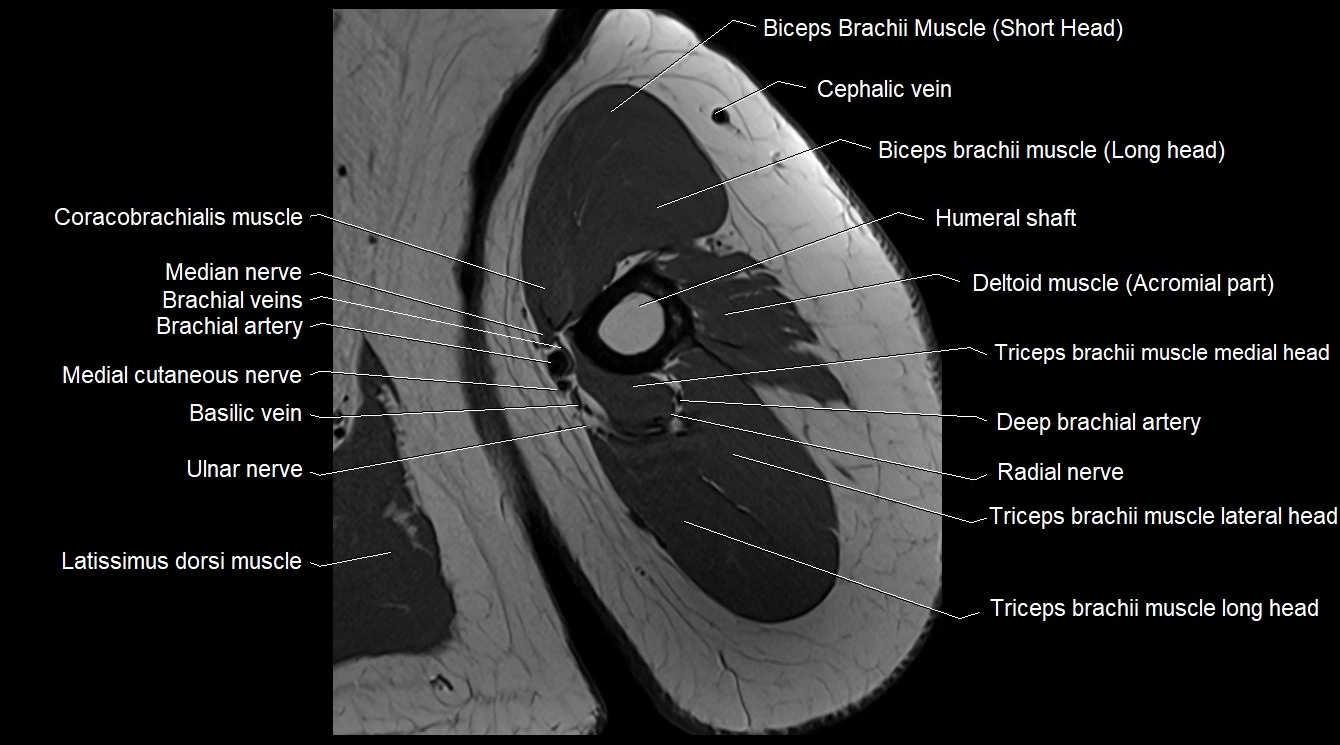

- Basilic vein

- Biceps brachii muscle

- Brachial artery

- Cephalic vein

- Coracobrachialis muscle

- Lateral head of triceps brachii muscle

- Latissimus dorsi tendon

- Long head of triceps brachii muscle

- Medial cutaneous nerve of forearm

- Medial head of triceps brachii muscle

- Median nerve

- Metacarpal bones

- Radial nerve

- Shaft (Body) of humerus

- Short head of biceps brachii muscle

- Triceps brachii muscle

- Ulnar nerve